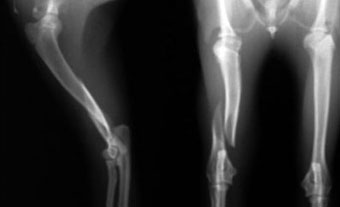

体重2.8kg、8か月齢の猫の上腕骨らせん骨折。

ピンニングと創外固定をタイインという方法で組み合わせることで、骨折部にメスを入れることなく整復固定しました。

写真上段: 手術前

写真中段: 手術直後